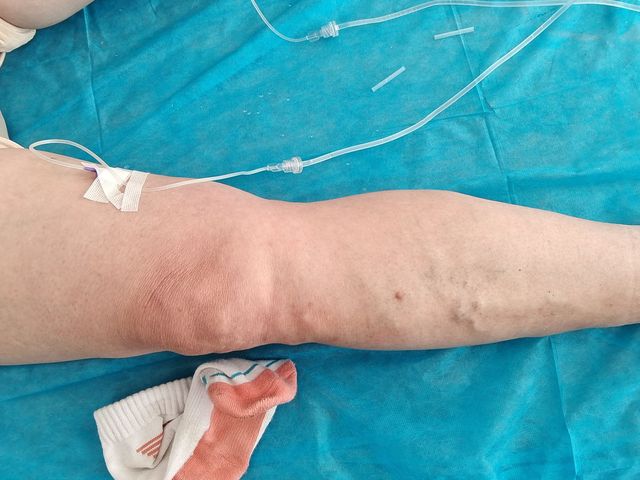

静脉曲张 王西艳

患者经弟弟介绍,在今天下午来到卫生院。患者今年58岁。

橘子香水手机像素好像不太好了。拍的不是很清楚。

薛医生你这腿静脉曲张的也不少,交通之也反流。这个价格可能会有点贵。一条腿得三千块钱。

橘子香水薛医生挨吵了。嘿嘿;-)薛医生给患者看的时候,患者没说大腿有。就按小腿的价算的钱。结果!正在排水呢!我问患者你大腿可有,她也说没有。我让她撸起来,就看到她的大腿上都是的。只是前面的比较轻,患者以为没有,而后面就重了患者又看不到。